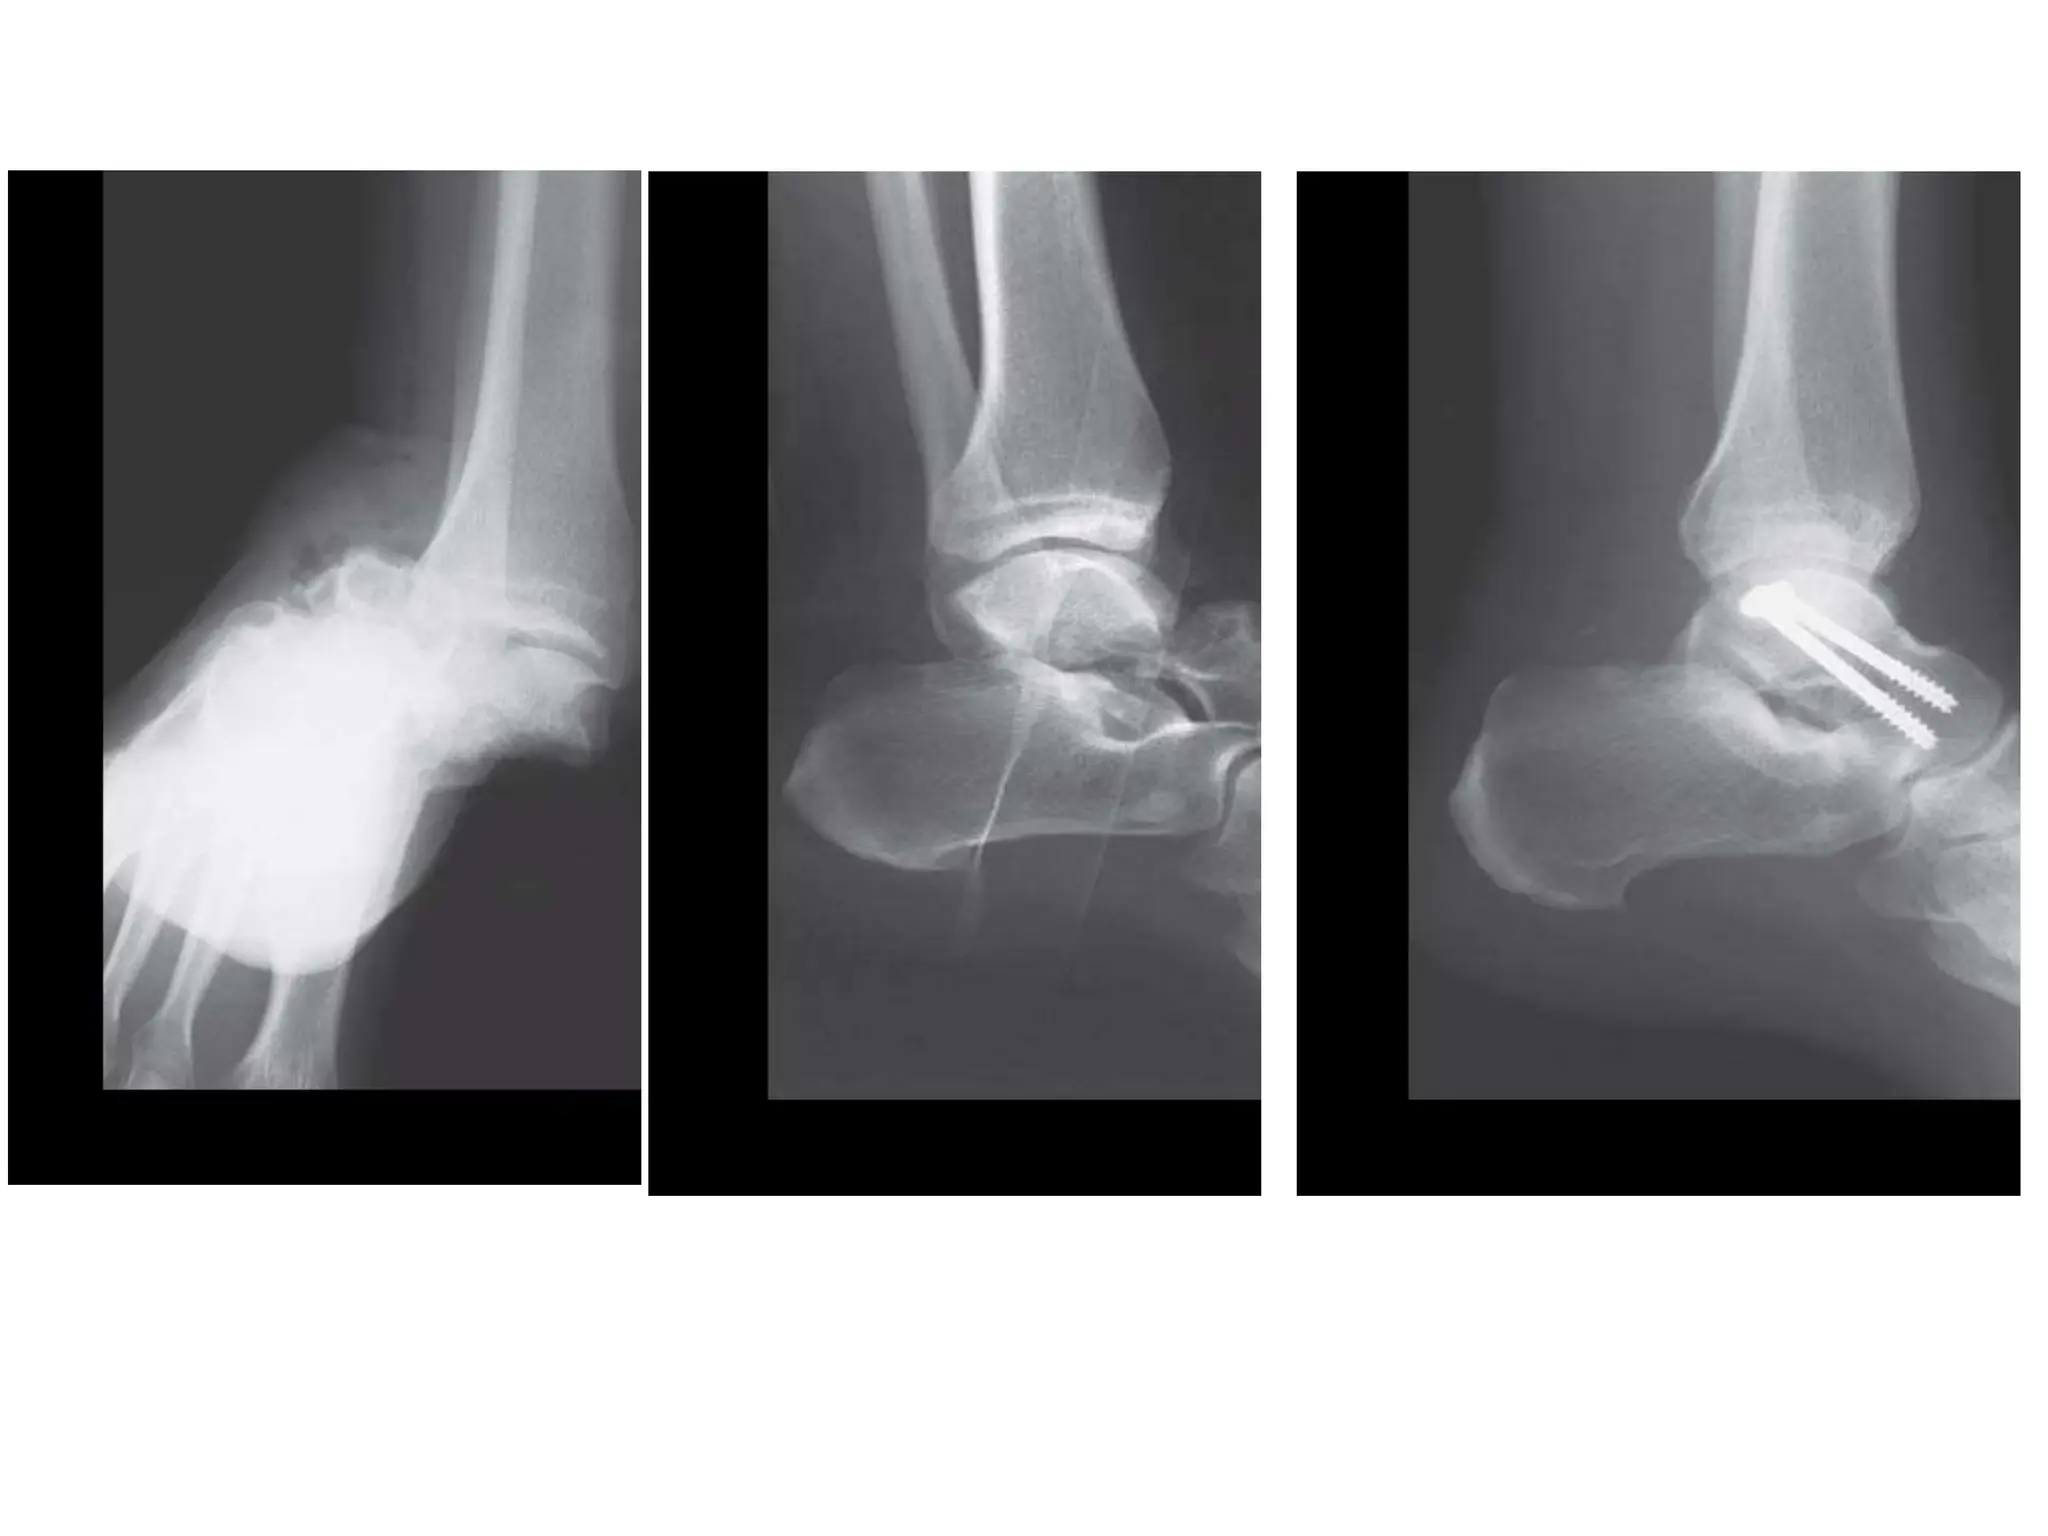

TALAR BODY FRACTURES

• Treatment strategy

similar to talar neck

fractures

• Medial or Lateral

Malleolar Osteotomy

frequently required

Visualize body through the fibula fracture